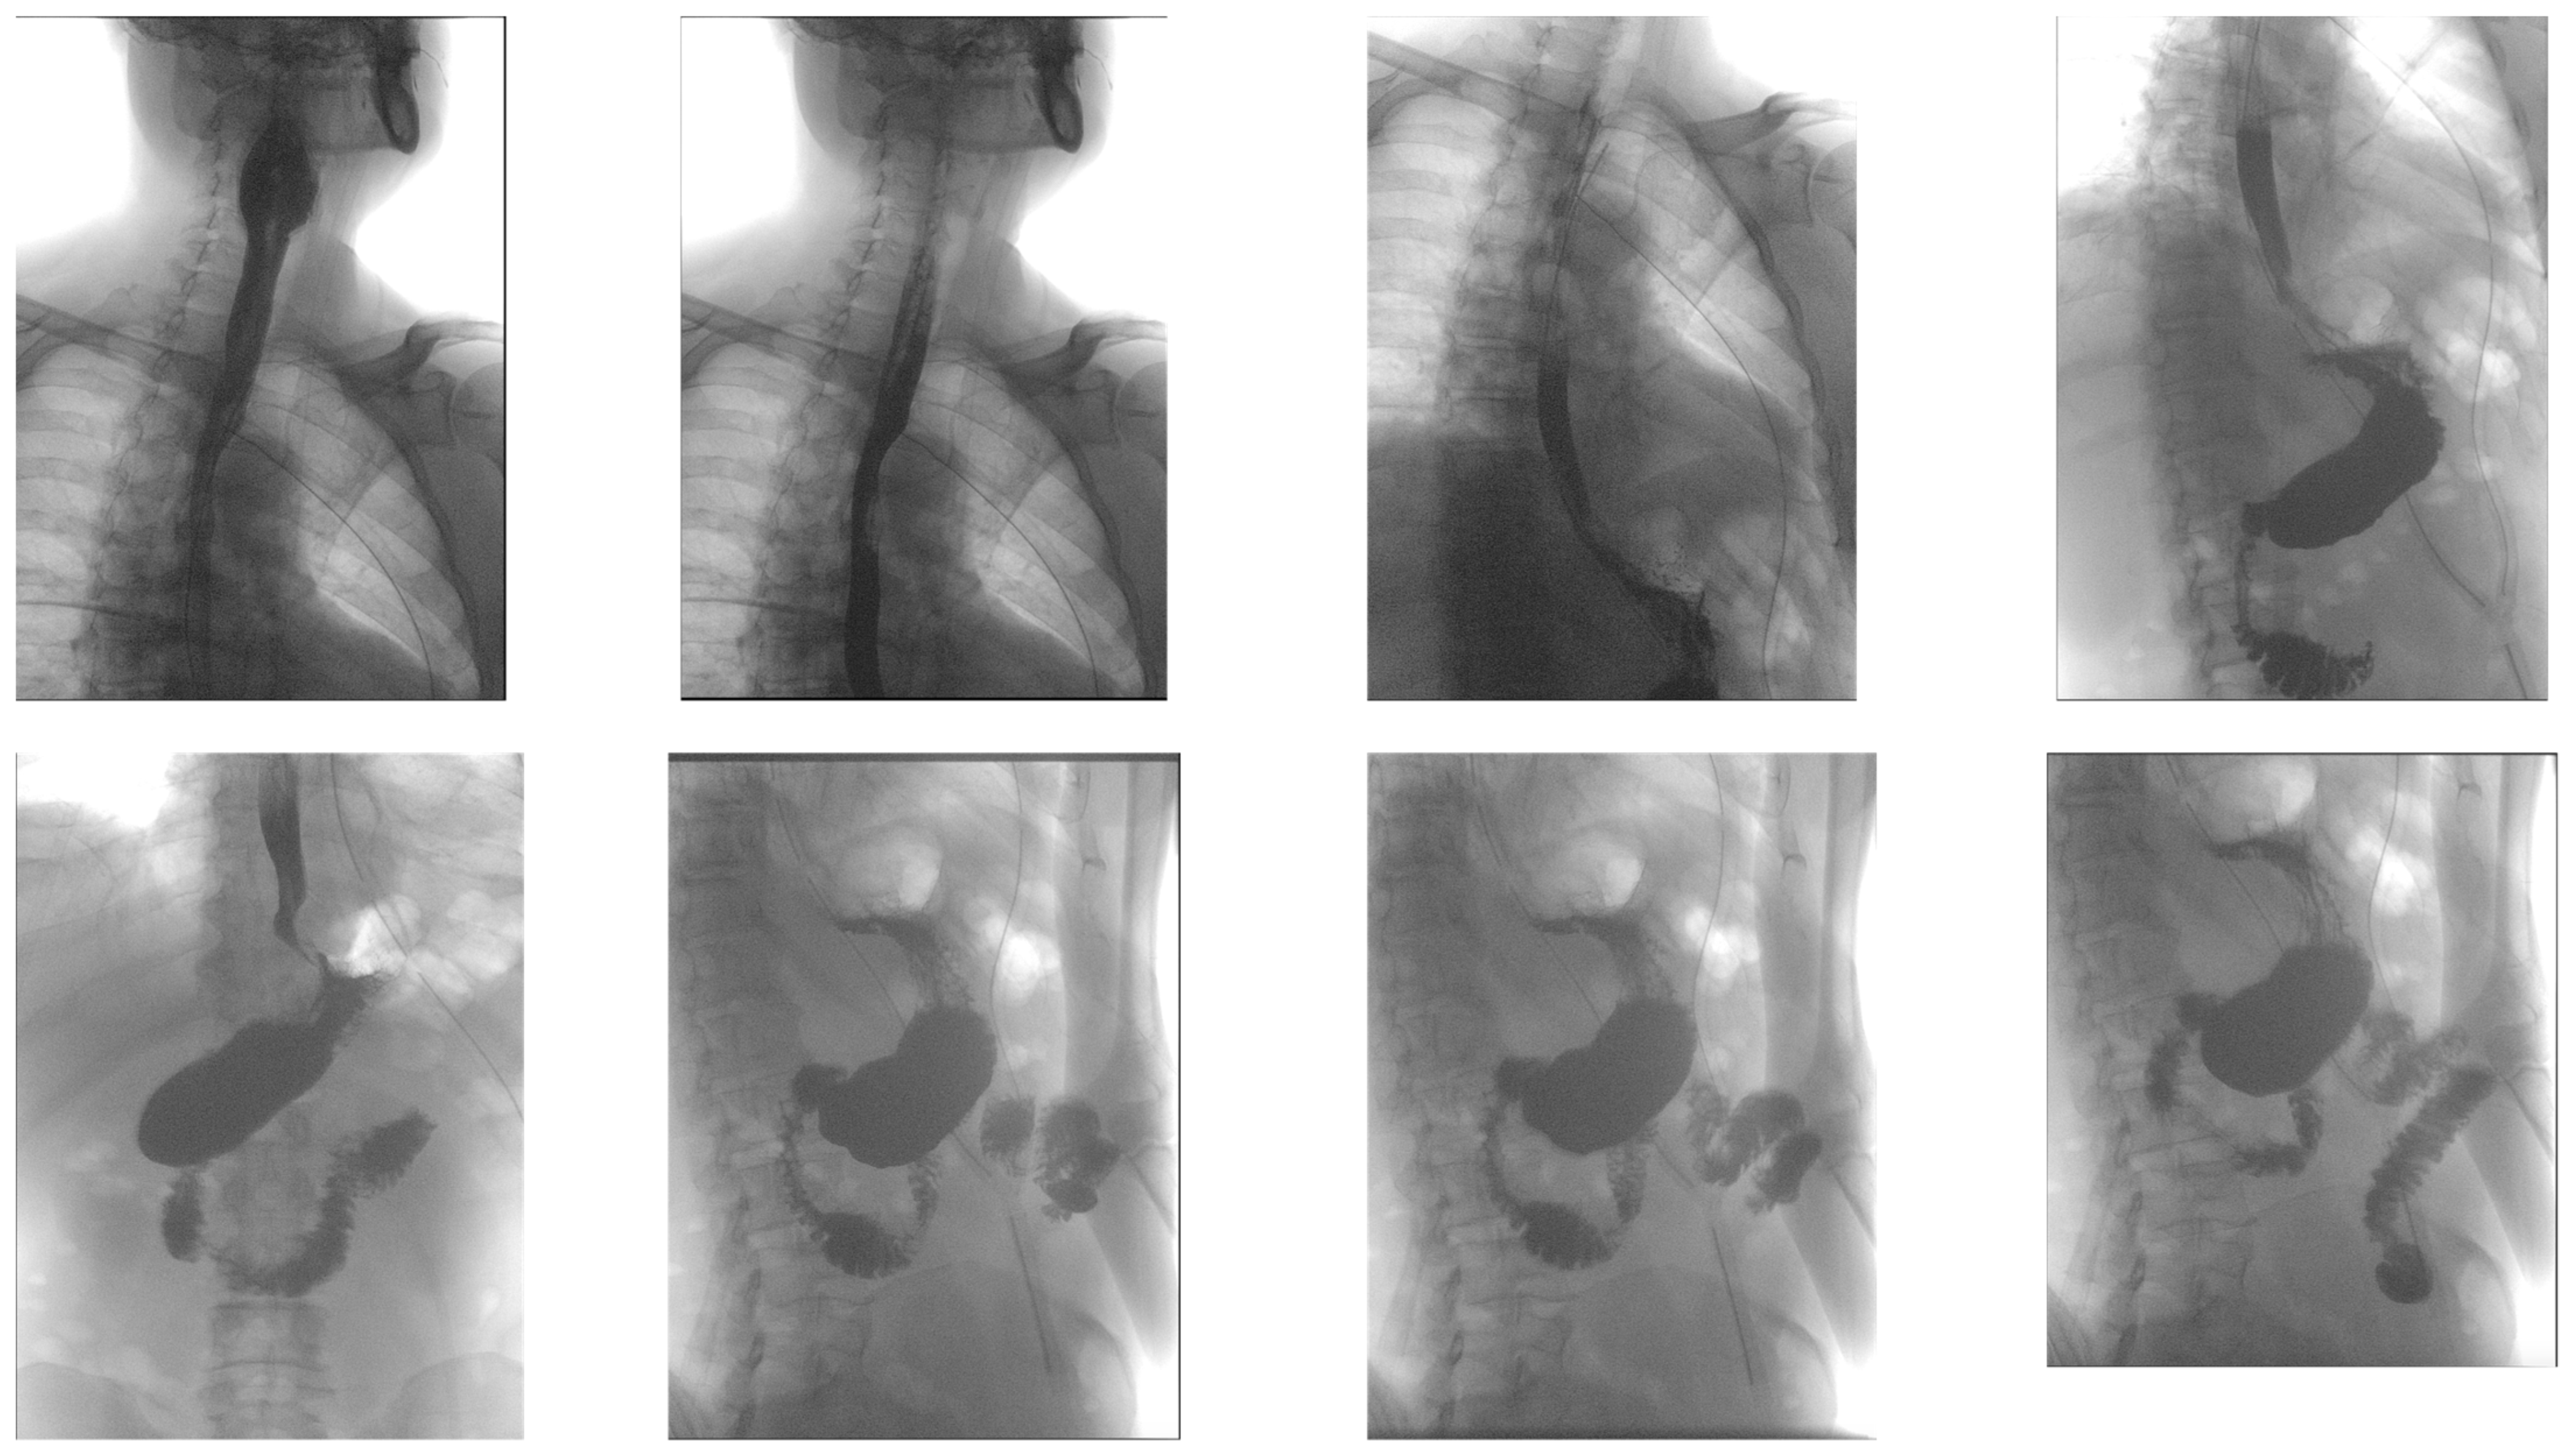

2. Case